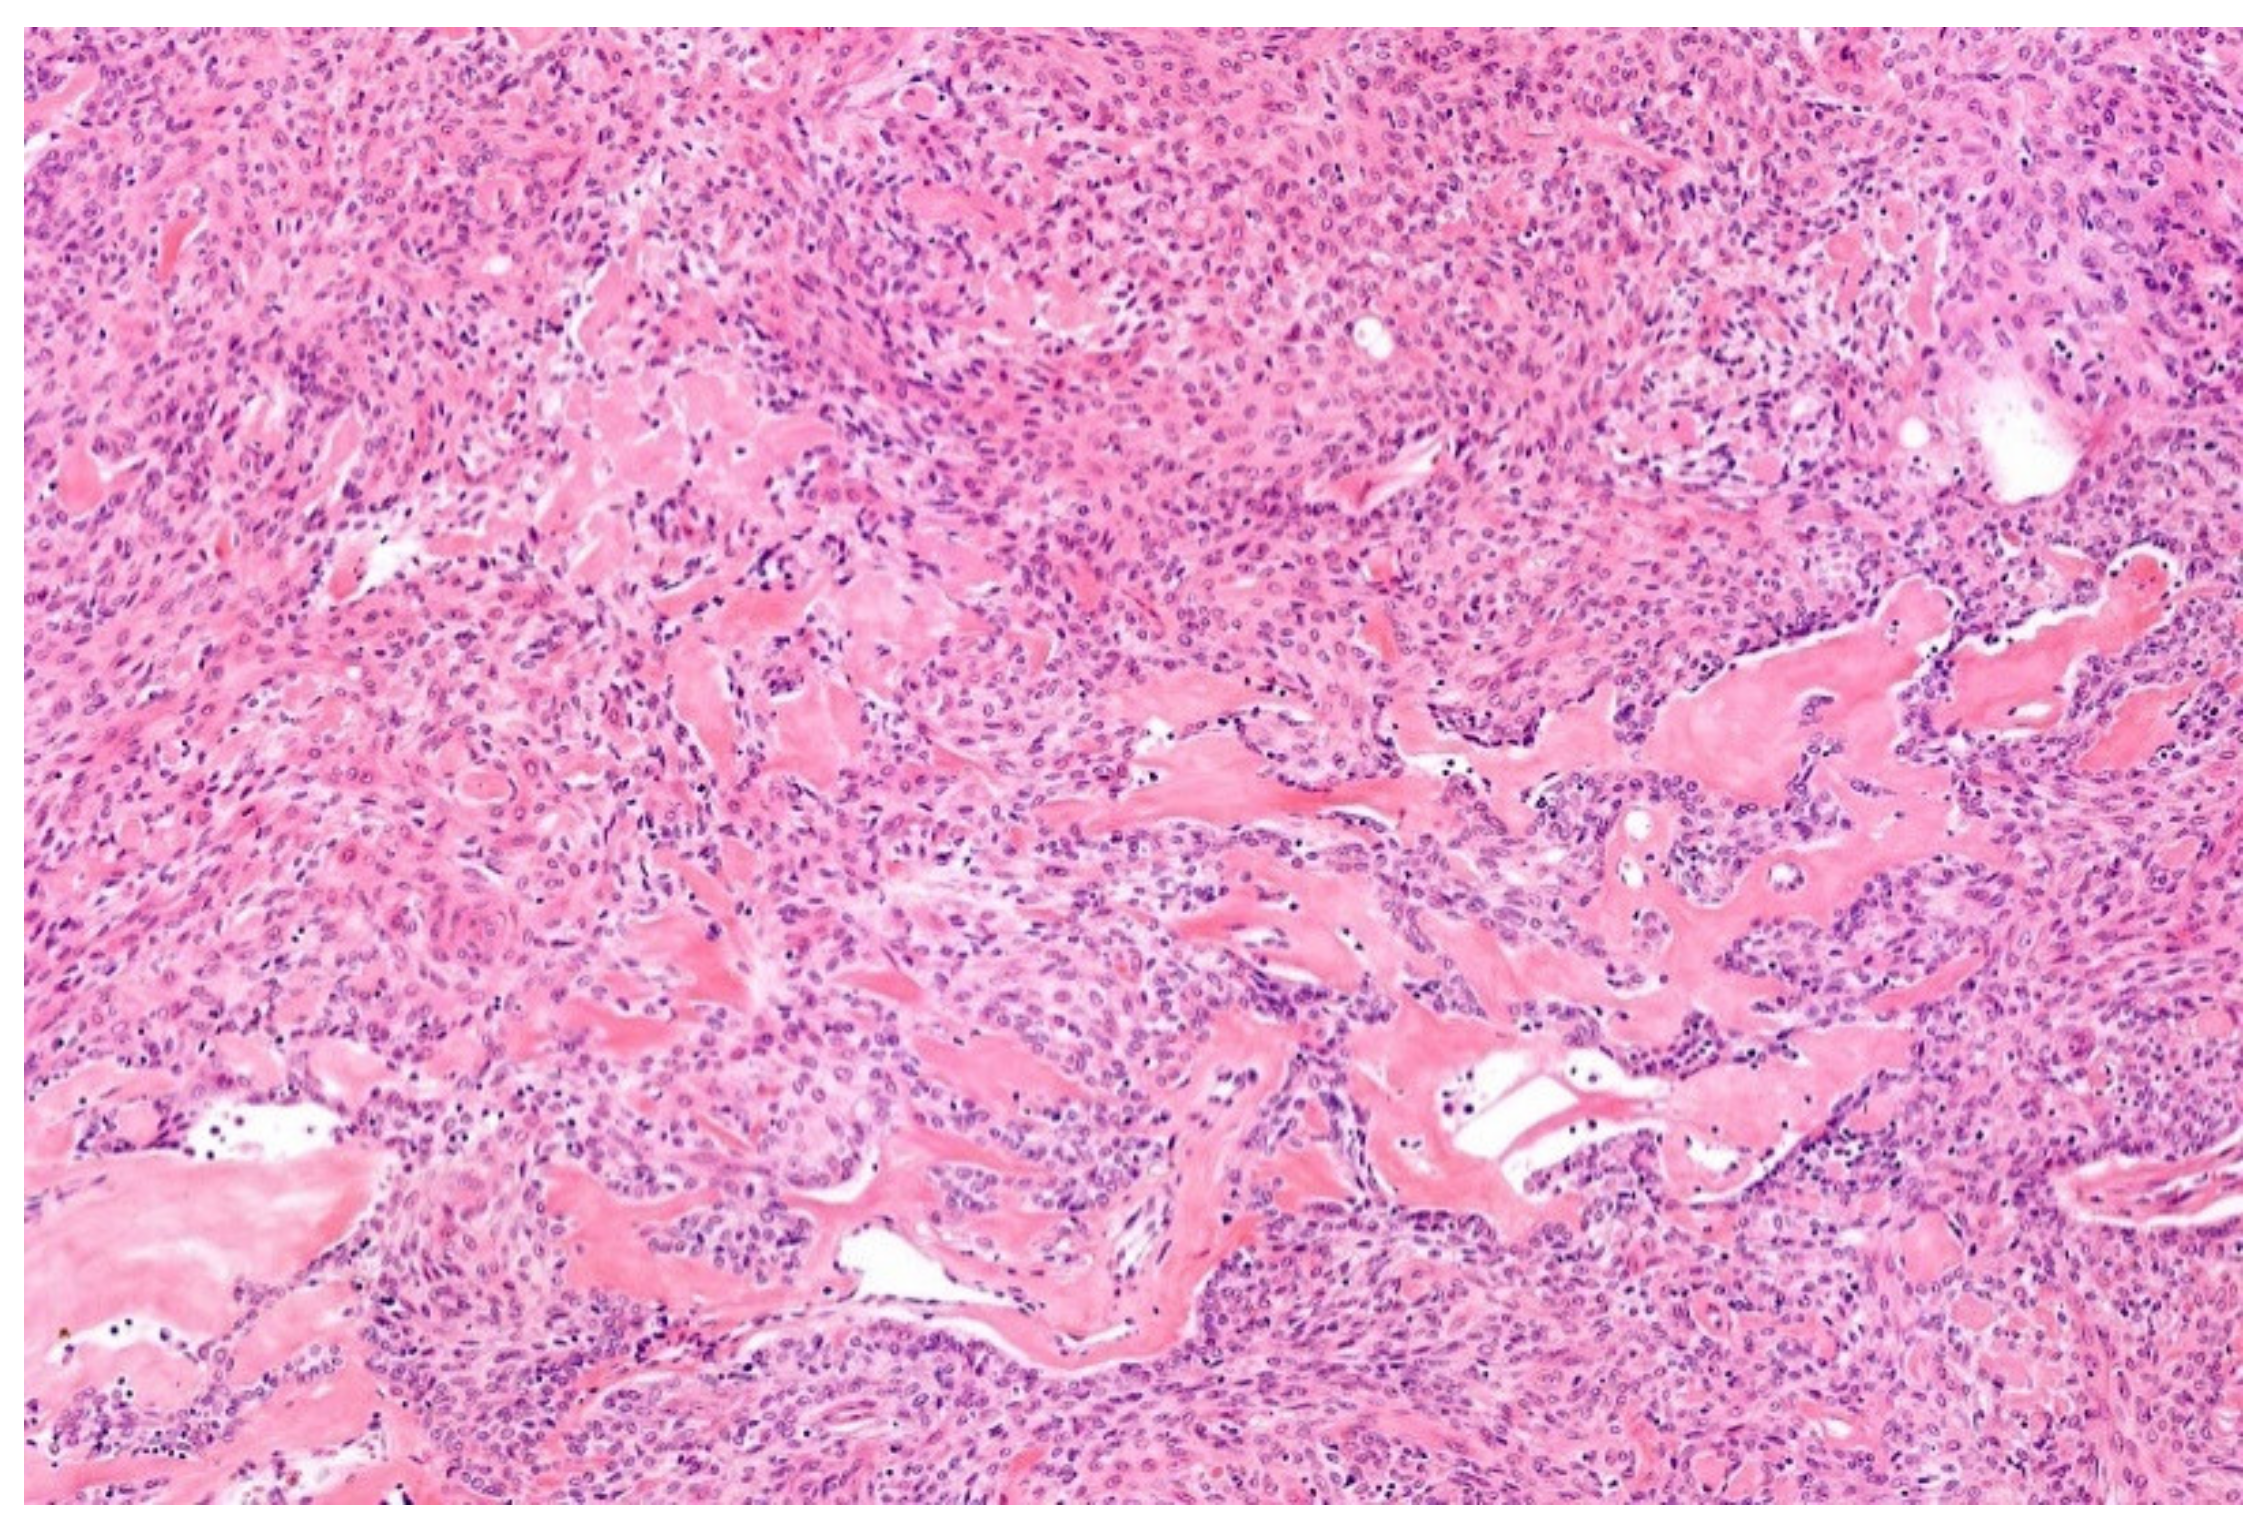

2. Ewing Sarcoma

3.1. NFATc2-Rearranged Sarcoma

3.2. EWSR1-PATZ and EWSR1-VEZF1 Rearranged Sarcoma